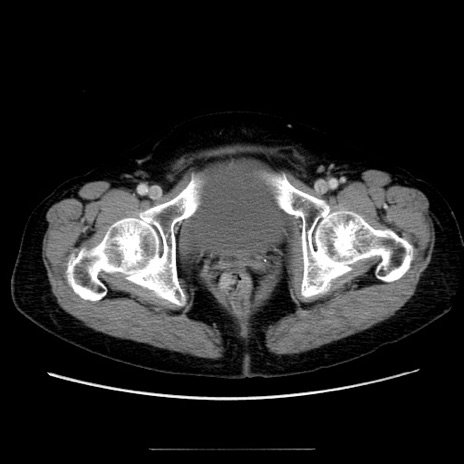

症例5(横断像)

【症例】70歳代女性

【主訴】お腹が張る

【現病歴】1週間くらい前から腹部膨満の自覚あり。昨日夜から増悪したため、本日救急外来受診。

【身体所見】意識清明、BT 36.5℃、BP 165/106mmHg、HR 80bpm、SpO2 98%、腹部:膨満、軟、自発痛・圧痛なし、触診にて不快感あり、腸蠕動音:減弱

【データ】WBC 12600、CRP 1.04